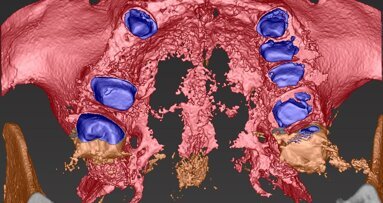

La paziente B.M. si rivolge, nell’anno 2002, alle cure di un odontoiatra in una città della Lombardia, per cui viene proposto e concordato un piano riabilitativo complesso consistente nell’inserimento di elementi implantari all’arcata superiore, specificatamente in posizione 13-14, 23-24 e 18 (Tuber mascellare, denominato anche impianto-pterigoideo), seguito da riabilitazione protesica fissa. Un altro impianto posizionato in sede 28 viene successivamente rimosso perché fallito. La situazione chirurgica definitiva risulta nella RX OPT mostrata nella Fig. 1.

Nella perizia del Consulente di Parte del 2003 (CTP iniziale, diverso dallo scrivente) si legge infatti: «All’esame ortopantomografico si nota: n. 3 pianti di destra di cui quelli in zona 13 e 14 scarsamente osteointegrati e presentanti una preoccupante invasione del cavo sinusale di destra (peraltro con note evidenti di opacità). A sinistra la presenza di n. 2 impianti endossei scarsamente osteointegrati e abbondantemente coinvolgenti la cavità sinusale di sinistra che presenta opacità diffusa».